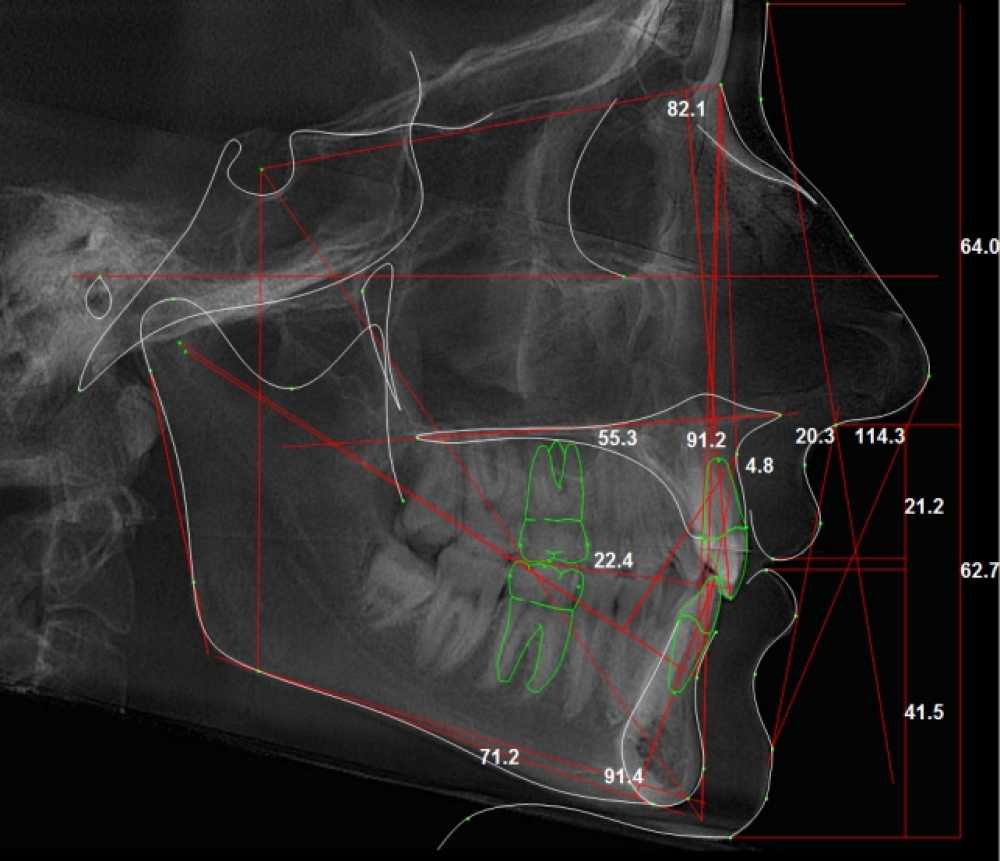

Діагностика в ортодонтії

- огляд основних етапів діагностичного процесу

- аналіз функціональних і структурних порушень

- сучасні методі діагностики

- формування плану лікування